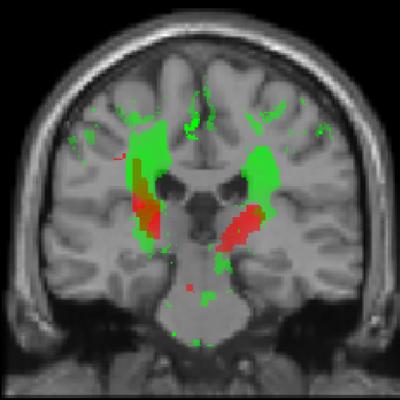

The scientists studied 13 patients with acute spinal cord injuries every three months for a year using novel MRI (magnetic resonance imaging) protocols. They discovered that the diameter of the spinal cord had rapidly decreased and was already seven percent smaller after twelve months. A lesser volume decline was also evident in the corticospinal tract, a tract indispensable for motor control, and nerve cells in the sensorimotor cortex. The extent of the degenerative changes coincided with the clinical outcome. "Patients with a greater tissue loss above the injury site recovered less effectively than those with less changes," explains Patrick Freund, the investigator responsible for the study at the Paraplegic Center Balgrist.